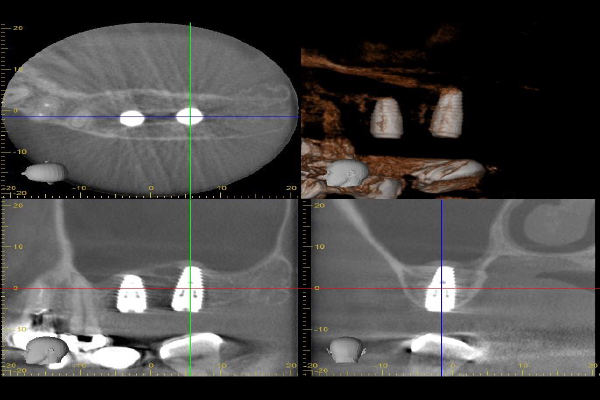

Case.02

インプラントの症例 インプラントの症例

治療前〜治療後のレントゲン写真

患者様の要望奥歯にインプラント治療したい

治療期間4ヶ月

治療費用880,000円

治療内容左上奥歯に2本インプラント埋入

治療のリスクネジが緩む可能性あり